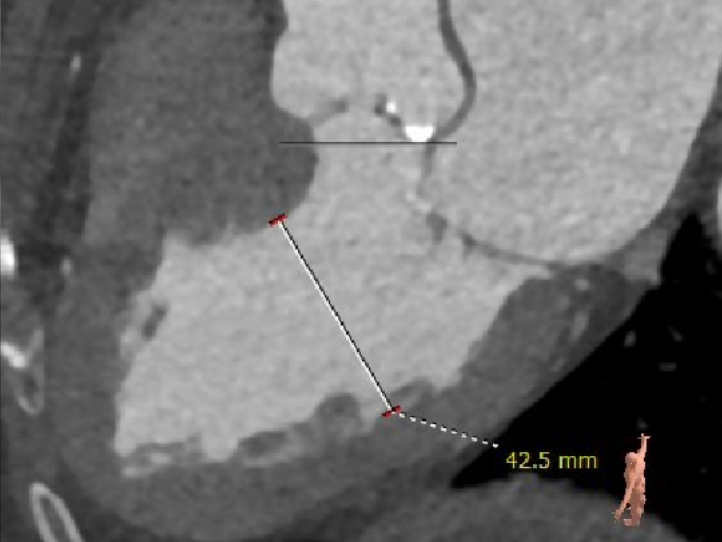

主动脉根部测量

主动脉瓣瓣环周长80.8mm,平均周长径 25.7mm,SOV:34.8mm*34.3mm*33.4mm,瓣叶增厚,瓣上见右无钙化嵴,瓣环水平夹角42°。

冠脉高度测量

左冠开口高度15.5mm

右冠开口高度20.0mm